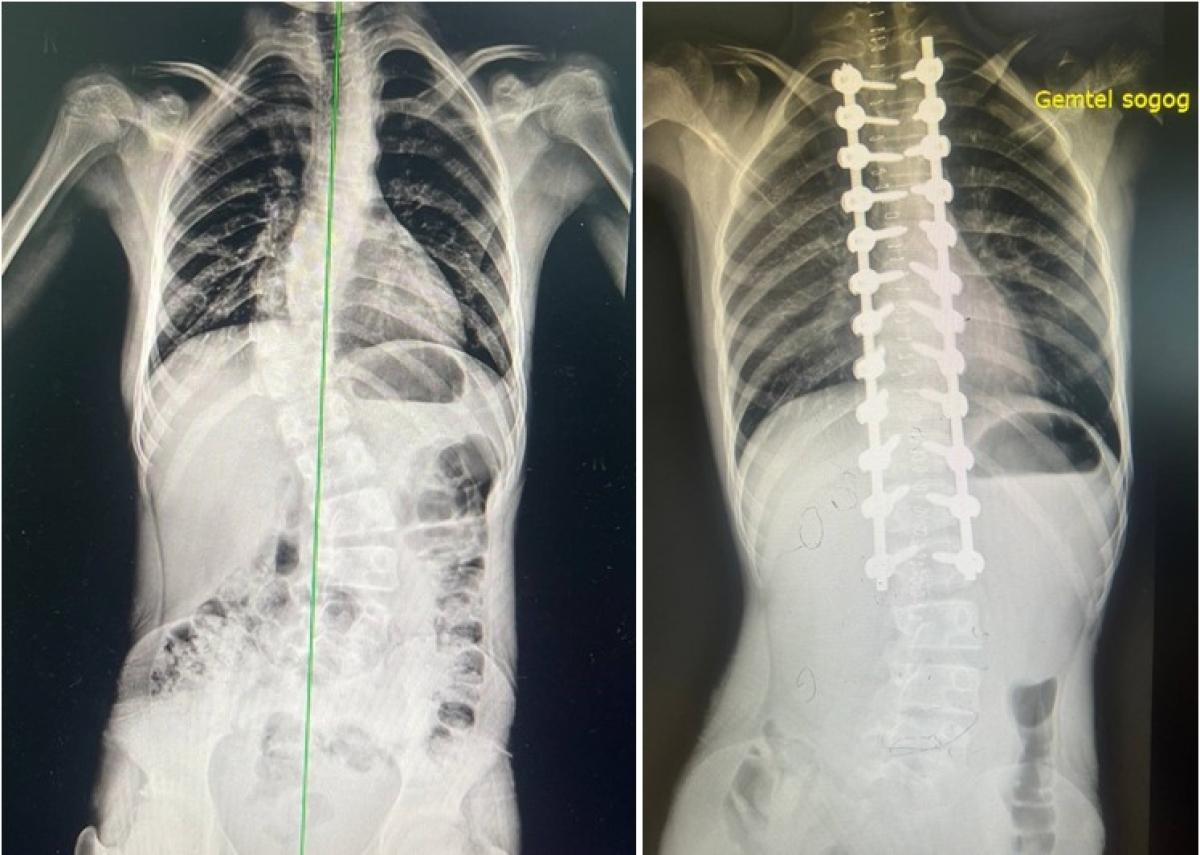

ГССҮТ, БНТУ-ын Истанбул хотын “Emsey” эмнэлэг хоорондын хамтын ажиллагааны дагуу тэрбээр өнгөрсөн зургадугаар сард тус төвийн Нурууны мэс заслын тасгийн эмч нартай хамтран нуруу, нугасны төрөлхийн хүнд гажиг, нурууны мурийлттай (Scoliosis) 12, 14 насны хоёр хүүхдэд мэс засал эмчилгээг амжилттай хийж байсан билээ.